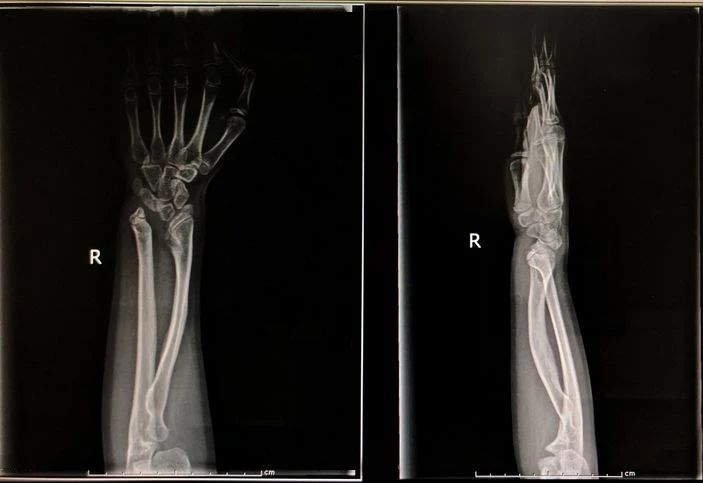

X线检查最擅长的就是看骨头,而且看得范围比较大,具有整体观的优势,手部X线可以检查前臂远端尺、桡骨等。

此外,X线还可检查前臂远端尺、桡骨等有无器质性病变,明确病变的部位、大小、程度及与周围软组织的关系,为治疗提供参考,目前仍是影像检查中使用最多和最基本的方法。